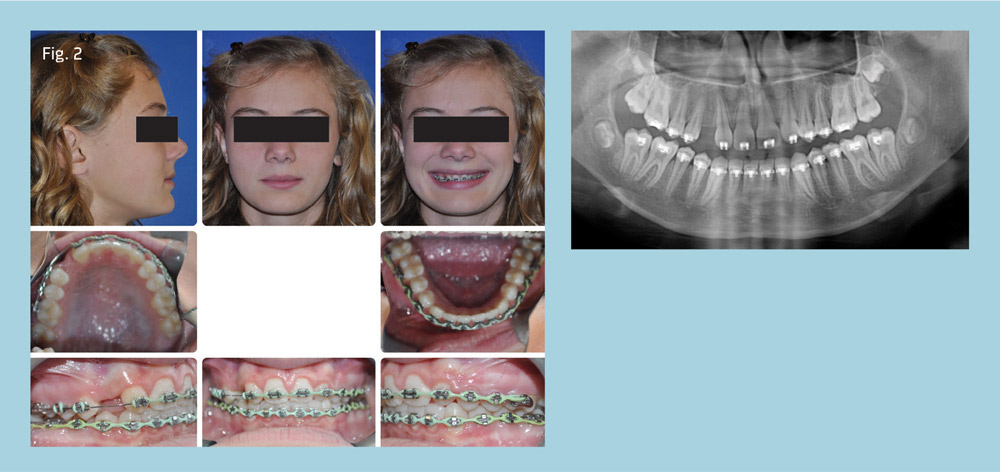

Our 11-year-old patient presented with congenitally missing teeth 7 and 10, skeletal Class I, dental Class II subdivision left, retro-inclined/upright maxillary incisors, good facial balance, and lip posture with a slightly obtuse nasolabial angle (Fig. 1).

Full brackets were placed and teeth 6 and 11 were reshaped by enamelplasty, then bonded with lateral incisor brackets. The first six months were spent consolidating space on upper arch, leveling the lower arch and idealizing overjet and maxillary incisor inclination. The challenge was improving anterior crown torque of the retro-inclined maxillary incisors. This was accomplished by using reverse curve in upper archwire, with opening coil between 6 and 5 to improve midlines and anterior torque (Fig. 2). This was also supported with Class III elastics.